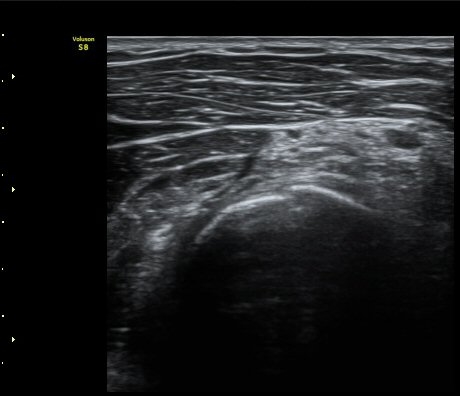

ÆÈ²ÞÄ¡  ¾ÕÂÊ¿¡¼­ ½ÃÇàÇÑ ¿ä°ñµÎ Á¾´Ü¸é°Ë»ç¿¡¼­ ƯÀÌ ¼Ò°ßÀ» º¸ÀÌÁö ¾ÊÀ½(±×¸² 1).

ÆÈ²ÞÄ¡ ¿ÜÃø¿¡¼­ ½ÃÇàÇÑ ¿ä°ñµÎ Á¾´Ü¸é°Ë»ç¿¡¼­ ¿ä°ñµÎ¿Í ¿ä°ñ °æ°èºÎ°¡ ¿¹°¢À¸·Î ÀÌÇàµÇ°í

°æ°èºÎ¿¡ ¼Ò·®ÀÇ ¼ö¾×Àú·ù°¡ °üÂûµÊ(±×¸² 2)